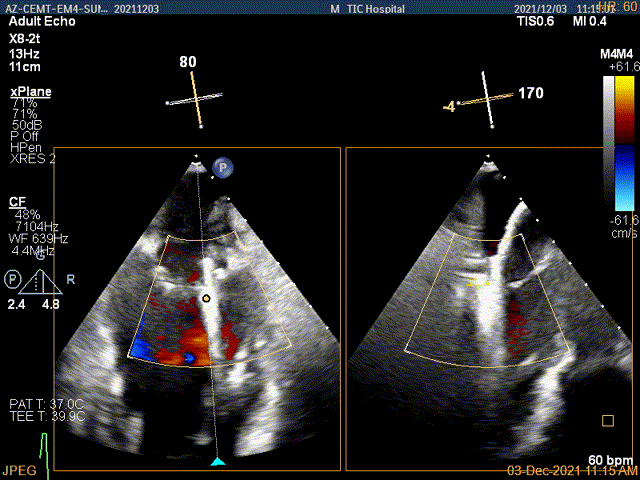

夹子关闭过程中,Color提示1区反流逐渐减少

二尖瓣口平均跨瓣压差:2mmHg

肺静脉血流频谱恢复正向

4Ch验证前后叶抓捕后有典型的bouncing征

3D-color证实无明确残余分流